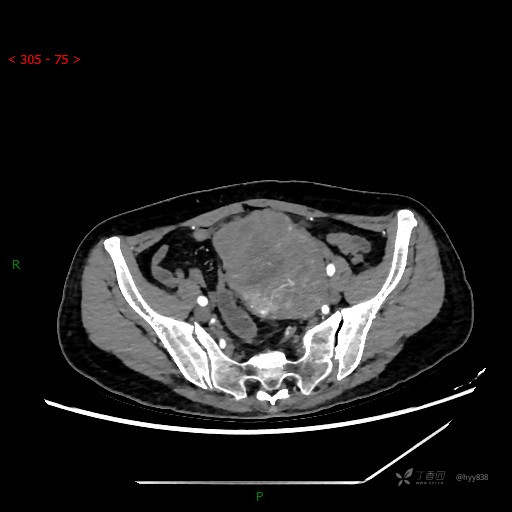

静脉期